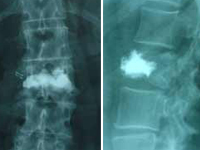

Kyphoplasty with balloon. Fracture of DX and DXI |